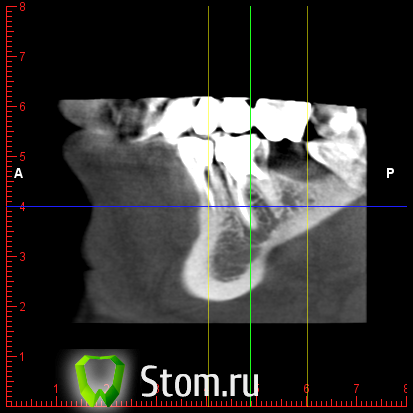

y2006 Опубликовано 3 мая, 2012 Автор Поделиться Опубликовано 3 мая, 2012 (изменено) прошу проконсультировать по поводу зуба 46. вопрос стоит в лечении и протезировании коронкой или удалении и заменой имплантом, правда ли что есть показания к удалению - перфорация корня? файлы для Romexis_Viewer по ссылке: (чуть позже)к сожалению не знаю как по другому выложить Изменено 3 мая, 2012 пользователем y2006 Ссылка на комментарий

y2006 Опубликовано 3 мая, 2012 Автор Поделиться Опубликовано 3 мая, 2012 снимок Ссылка на комментарий

y2006 Опубликовано 3 мая, 2012 Автор Поделиться Опубликовано 3 мая, 2012 (изменено) какие есть методы лечения? или есть необходимость в дополнительных проекциях? Изменено 3 мая, 2012 пользователем y2006 Ссылка на комментарий

y2006 Опубликовано 5 мая, 2012 Автор Поделиться Опубликовано 5 мая, 2012 (изменено) КТ IMAGES.rar46 зуб Изменено 5 мая, 2012 пользователем y2006 Ссылка на комментарий